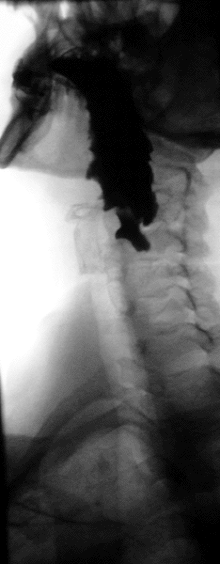

رتج زنكر[1] (بالإنجليزية: Zenker's diverticulum) أو الرتج البلعومي المريئي[1] أو رتج المريء العلوي هو عبارة عن رتج يحدث عند التقاء البلعوم مع المريء، حيث تكون هذه المنطقة ضعيفة. ويكون رتج زنكر على شكل كيس، قد يحدث هذا الرتج نتيجة تناول لقمة طعامية مبالغ في حجمها، أو يحدث نتيجة تشوه معين مما يسبب تمزق في مخاطية البلعوم تسمح بتدلي الغشاء المخاطي في هذه المنطقة الضعيقة ضمن المسافة خلف البلعوم على شكل كيس يدعى: رتج زنكر, يشاهد غالباً عند الرجال بعد سن الخمسين, وسببه تقلص مصرة البلعوم السفلية على مصرة مريئية علوية لم تنفتح بالكامل أثناء البلع فيرتفع الضغط على مخاطية المريء ومع الوقت يحدث الانفتاق.[2]

التشخيص

إما بالتصوير الشعاعي الظليل أو بالتنظير تحت الرؤية المباشرة.